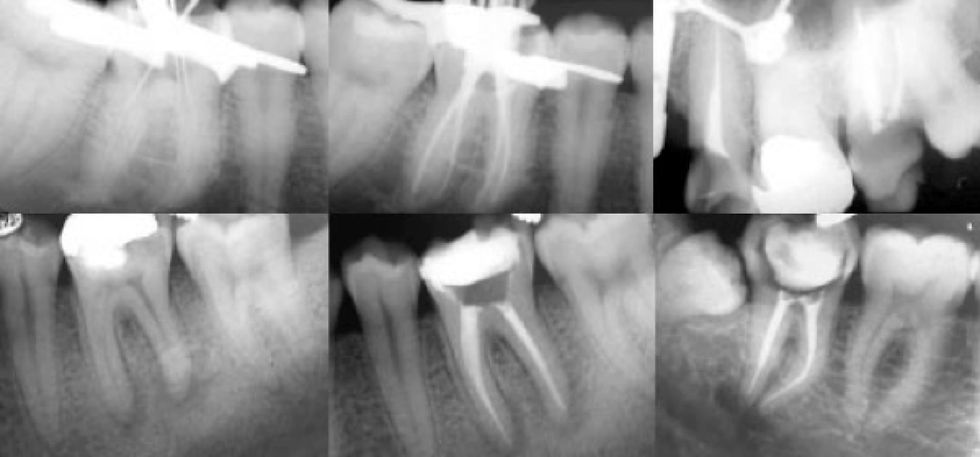

Endodoncia

En el interior del diente encontramos a la pulpa dental que es un tejido conectivo altamente especializado, de sus funciones la que es mas reconocida es la de generar dolor dental. Cuando sufre algún daño o enfermedad, ésta puede morir causando hipersensibilidad, dolor dental agudo, fuertes infecciones y decolorar el diente hasta dejarlo gris e incluso negro en casos extremos. El especialista en esta rama de la odontología, ejecuta tratamientos con la mas alta y de vanguardia tecnología a nivel mundial.